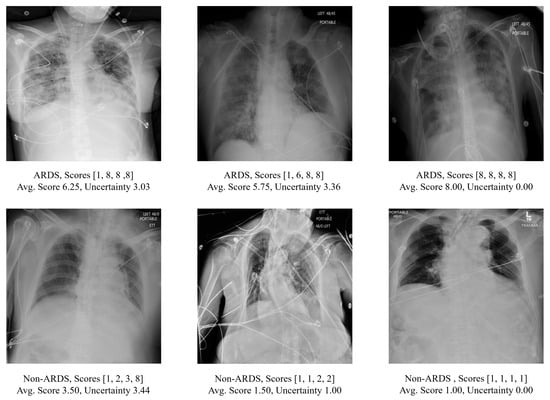

3.3. Qualitative Results Using the Score-CAM Approach on Test Images

Visualizations of the CXR images and their corresponding ScoreCAM heat maps from the proposed method are presented in Figure 5. The highlighted areas signify regions of interest during the model’s decision-making process for relevant classes. The upper panel exhibits the true positive cases, the middle panel displays true negative predictions, and the lower panel showcases highlighted regions when the model produces false positive or false negative predictions. In instances of true positive predictions, the areas of interest predominantly focus on lung regions that exhibit consolidations. True negative predictions see the model emphasizing the overall lung region and its corners. For incorrectly predicted cases, the model either concentrates on the region of interest but fails to make the correct prediction or is unable to highlight the correct region of interest. In addition, despite the existence of various medical devices, the model has not erroneously emphasized them in its predictions. This indicates the model’s robustness against confounding structures.

Figure 5.

Image pair featuring the original CXR alongside ScoreCAM heatmap-overlaid CXRs. The text below each image pair indicates the ground truth ARDS label and the probability of ARDS as predicted by the target model.